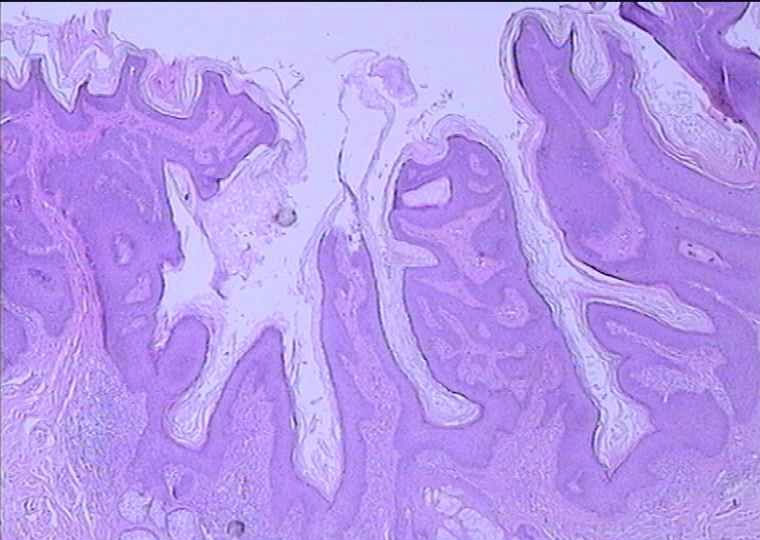

男 48岁 ,头部肿块48年(出生有),1CMX1CM,

皮脂腺痣

皮脂腺痣,表皮有增生

表皮呈疣状增生,真皮内见到大量近乎成熟的皮脂腺